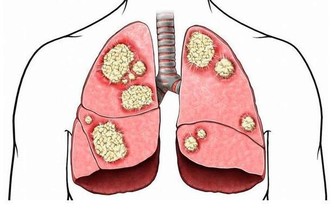

例如一位骨折病人,他 曾在一段時期內被限制運動,那麼他就容易發生靜脈血栓,

而靜脈血栓一旦掉下來,則可能發生肺梗死。

5.久坐:長期上網屬於靜態性動作,血液粘稠度較高,下肢可能形成深靜脈血栓,

運動時血栓脫落,可能會造成肺梗塞,嚴重可能導致猝死。